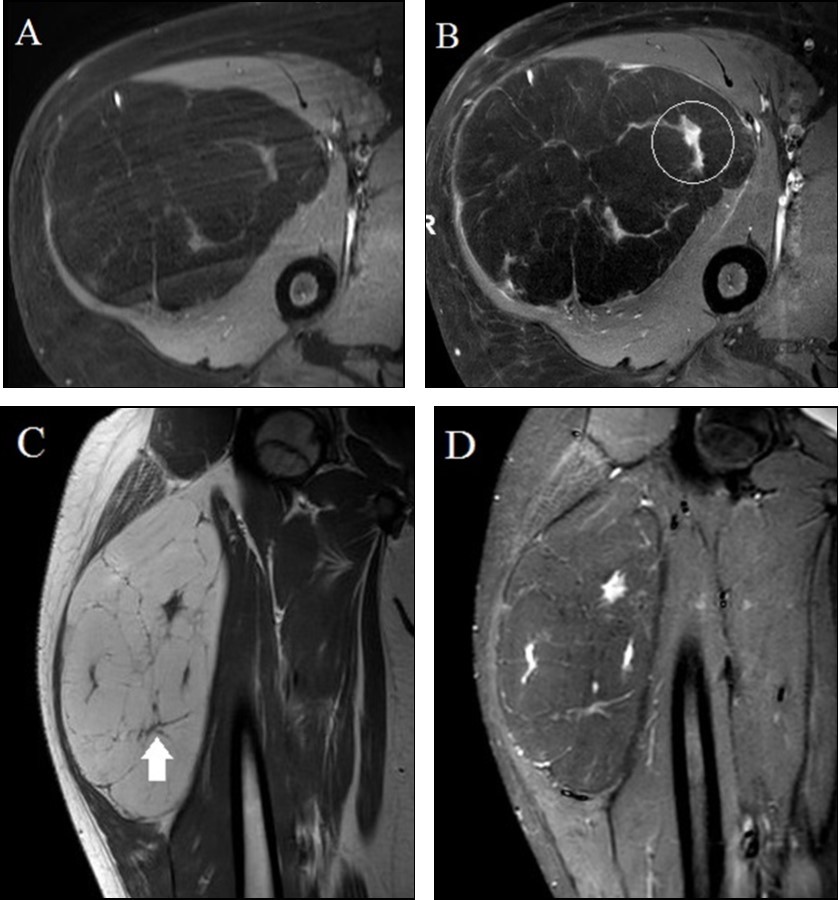

A 13 year old male presented to his local physician with a painless, slowly enlarging palpable mass of the proximal right thigh. Contrast-enhanced MRI was performed which raised concern for soft tissue sarcoma. We were consulted for a second opinion interpretation of the imaging study and recommendations for management. Outside multi-planar and multi-weighted MRI demonstrated a large lipomatous anterior compartmental thigh mass (Figure 1A-D). The mass was predominantly fatty with the majority of the tumor following the signal intensity of subcutaneous fat on both T1-weighted and fat-suppressed images. Internal enhancing nodularity (Figure 1B) and slightly thickened septations (Figure 1C) argued against simple lipoma and did initially raise concern for liposarcoma; however, liposarcomas are extremely rare in children. MRI findings of a slightly complex mostly fat containing mass with mild nodularity and thin internal septations are often seen in atypical lipomatous tumors. While greater than most reported lipoblastomas, patient age was felt to be more suggestive of lipoblastoma than ALT. Imaging features were not consistent with a simple purely fatty lesion such as lipoma and lack of any dominant internal non-adipocytic soft tissue elements argued against dedifferentiated liposarcoma. Under the care of an outside orthopedic surgeon, the patient underwent uncomplicated resection of the mass with negative margins and recovered well following surgery; gross tumor size and description of capsule at outside surgery are not available. Histopathology confirmed a lipomatous neoplasm with mature appearing white adipocytes lacking atypia or nuclear pleomorphism and several internal fibrous septae (Figure 2). Additionally, numerous interspersed multivacuolated brown fat cells with granular eosinophilic cytoplasm were identified yielding a final unexpected pathologic diagnosis of hibernoma.

Figure 1.13 year old male with a fatty proximal right thigh mass. A-B. Axial unenhanced (A) and gadolinium-enhanced (B) fat-suppressed T1-weighted turbo spin echo images demonstrate an anterior compartmental mass largely demonstrating similar signal intensity to subcutaneous fat with internal enhancing nodularity (circle in B). C-D. Coronal T1-weighted turbo spin echo (C) and short tau inversion recovery (D) images demonstrate internal thin internal septations (arrow in C) and internal nodularity with increased STIR signal intensity.